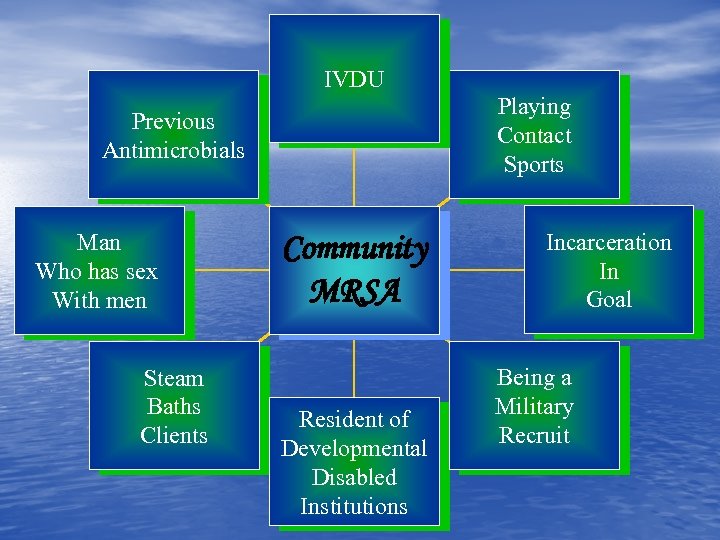

IVDU Playing Contact Sports Previous Antimicrobials Man Who has sex With men Steam Baths Clients Community MRSA Resident of Developmental Disabled Institutions Incarceration In Goal Being a Military Recruit

IVDU Playing Contact Sports Previous Antimicrobials Man Who has sex With men Steam Baths Clients Community MRSA Resident of Developmental Disabled Institutions Incarceration In Goal Being a Military Recruit